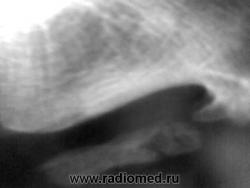

Изменения по подошвенной поверхности стопы.

Боли в области стопы.

Шпоры пяточной кости (и в месте прикрепления ахиллова сухожилия, и в месте прикрепления подошвенного апоневроза) в сочетании с выраженным окостенением подошвенного апоневроза.( По Д.Г. Рохлину-это локальные проявления преждевременного старения костно-суставной системы.)

Тендиноз в области пяточного бугра. Окостенение подошвенного апоневроза может быть травматического характера, может связанного с профессией.

Спасибо за комментарии! Я в заключении написал, что выше отметили коллеги: "Оссификация подошвенного апневроза".Цель демонстрации: за 25 лет работы столь выраженные изменения, вижу впервые.Не уверен, что есть перелом оссифицированного апоневроза.

Если честно, то не знаю. С.А.Рейнберг определят подобные состояния, как метаплазию мягких тканей в костную ткань. Этиологию, которую предполагал автор, точно не помню ("нельзя объять неоъятного"), но можно ещё раз вернуться к этой прекрасной книге.